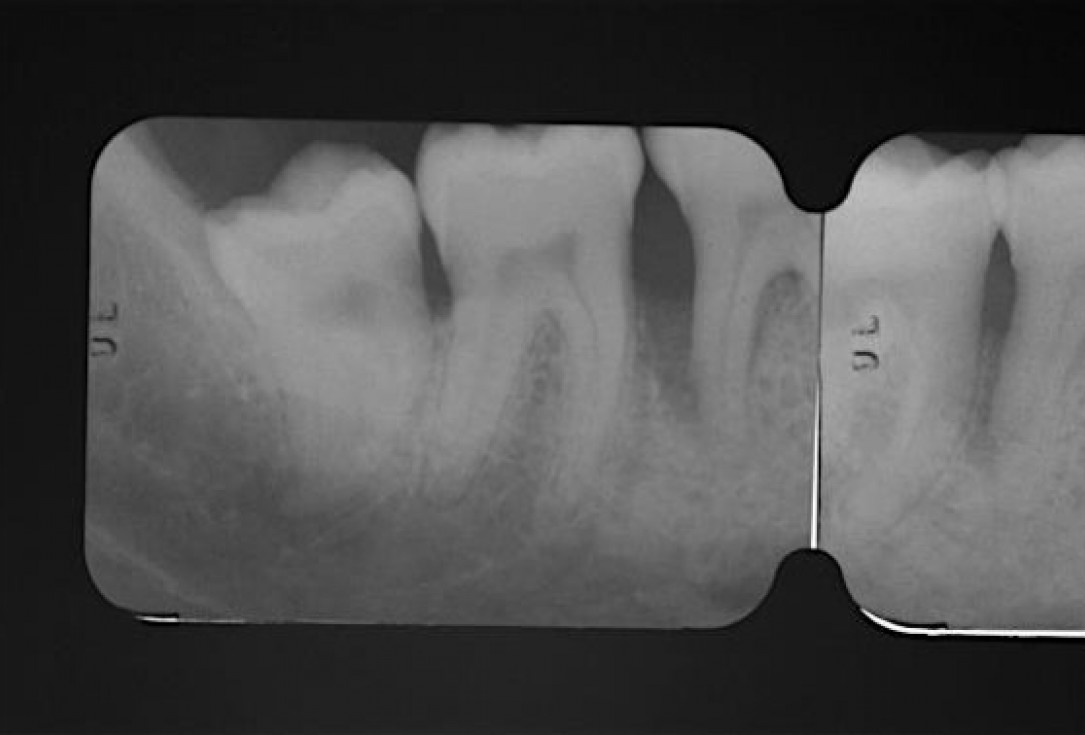

Radiographic view before periodontal regenerative therapy with Straumann® Emdogain®. A deep intrabony defect appeared mesially and distally on the left mandibular first premolar. Pre-surgical probing measured 8 mm. The defect morphology presented as well-contained.